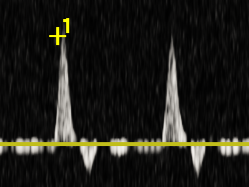

Zapis dopplerowski z tętnicy- małe zmiany miażdżycowe.

Zapis dopplerowski z tętnicy- duże zmiany miażdżycowe ze zwężeniami.